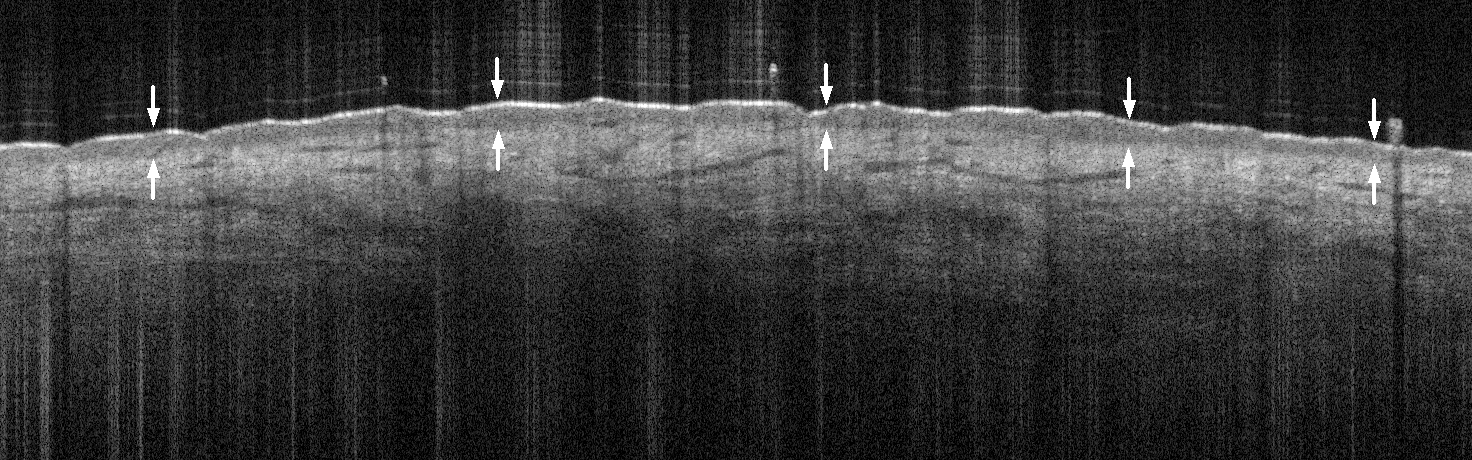

Epidermis

- Top layer of skin starting at the band of hyperreflectivity

- Heterogeneous granular texture due to cells with differing intracellular keratin content

- Thin Stratum Corneum sometimes observed beneath the hyperreflective band caused by surface reflection

- Thickness changes can be observed in different anatomical regions, hydration states and pathologies